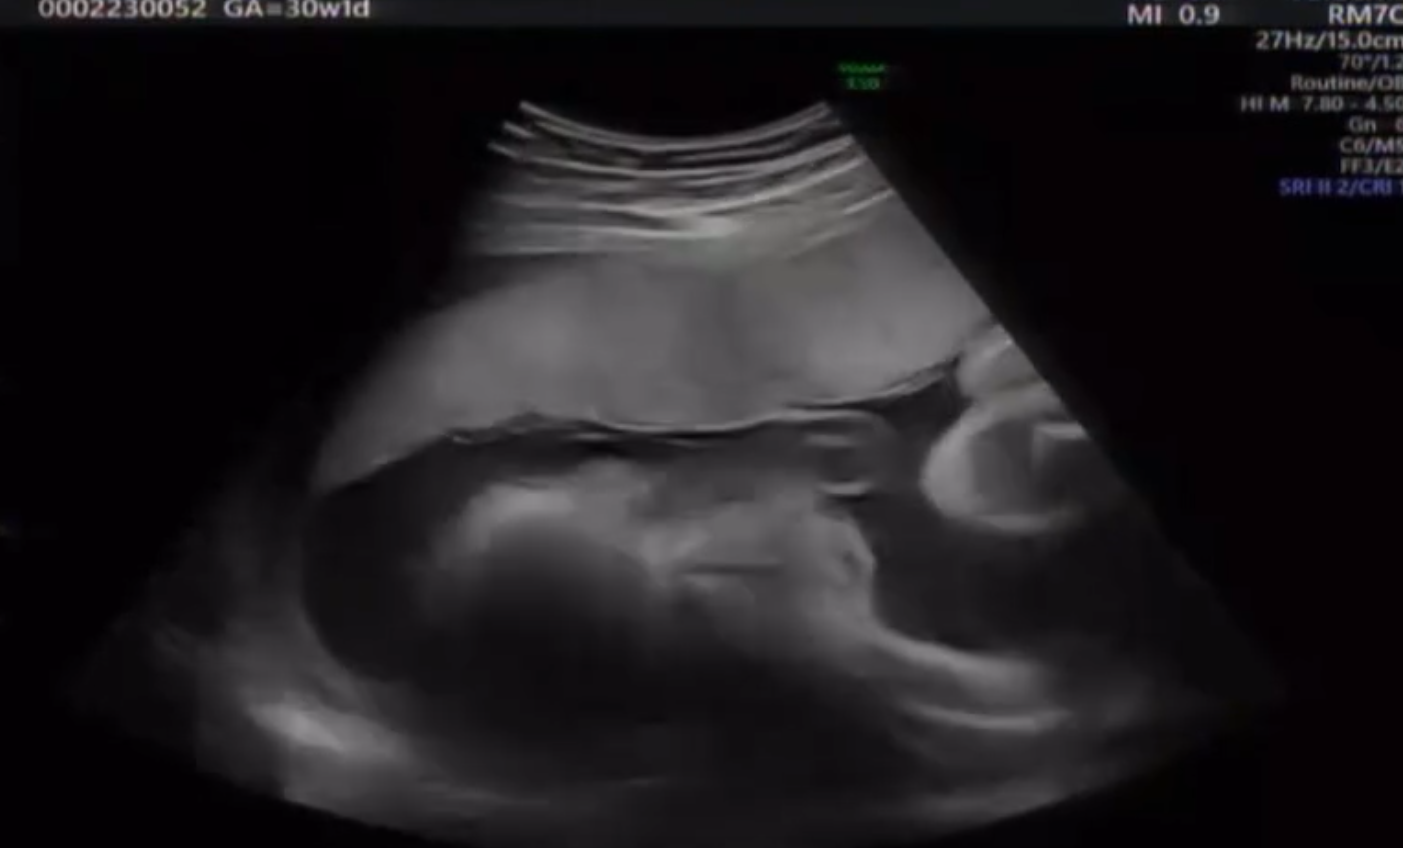

妊娠30週のエコー 映った顔に…「ホラー」「こんなハッキリ映るんですね」「めっちゃ元気」「心霊写真」「主張激しめ」